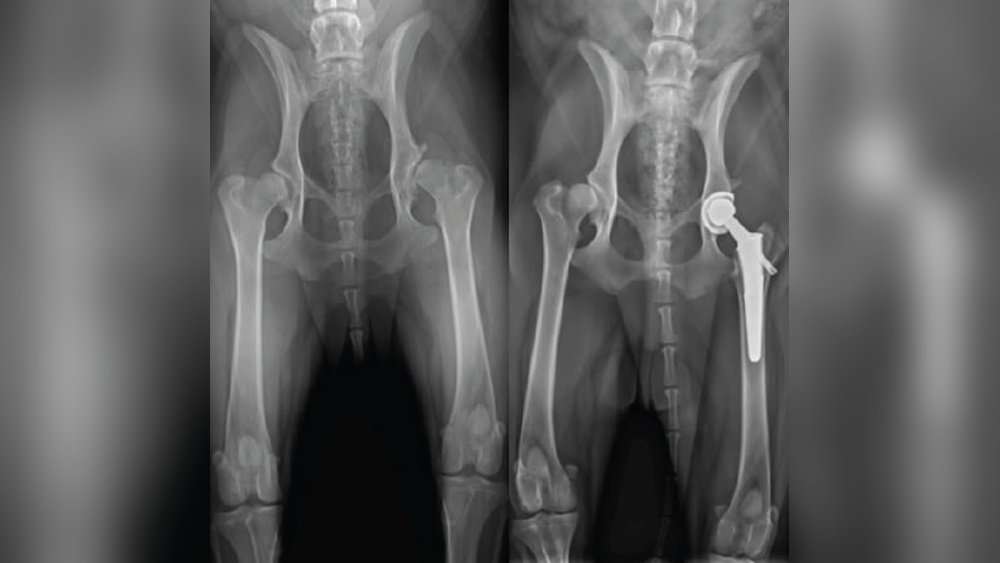

How Much is Hip Surgery on a Dog: Essential Cost Guide 2026

If your dog is struggling to move or seems in pain, you might be wondering how much hip surgery will […]